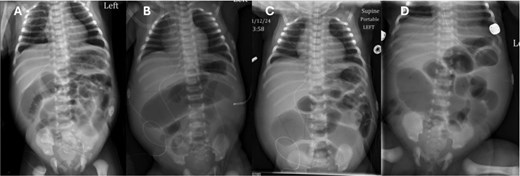

On day of life (DOL) 6, she was noted to have a melanotic stool with increased abdominal distension. Repeat AXR showed presumed dilated transverse colon (Fig. 2). There was concern for infectious pathology, however blood cultures, urine cultures, and cytomegalovirus serology later resulted as unremarkable. DOL 10 AXR (Fig. 2) illustrated new linear lucencies, possible pneumatosis, and patient was taken to the operating room.

Progression of AXR. Note the changing bowel gas patterns. (A) DOL 2. (B) DOL 5. (C) DOL 6. (D) DOL 10 with concern for pneumatosis.

AXR is a useful diagnostic tool in early evaluation of intestinal atresia. Duodenal atresia, which has a different etiology than small bowel atresia, presents with the diagnostic "double bubble" on AXR. When the atresia is located more distally in the jejunum, the AXR will have more than two bubbles. The patient presented failed to have any of the classical findings of obstruction due to incomplete blockage of the intestine. The AXR shown in Fig. 2 clearly demonstrates a large amount of air passing through the intestine without an obvious area of obstruction.